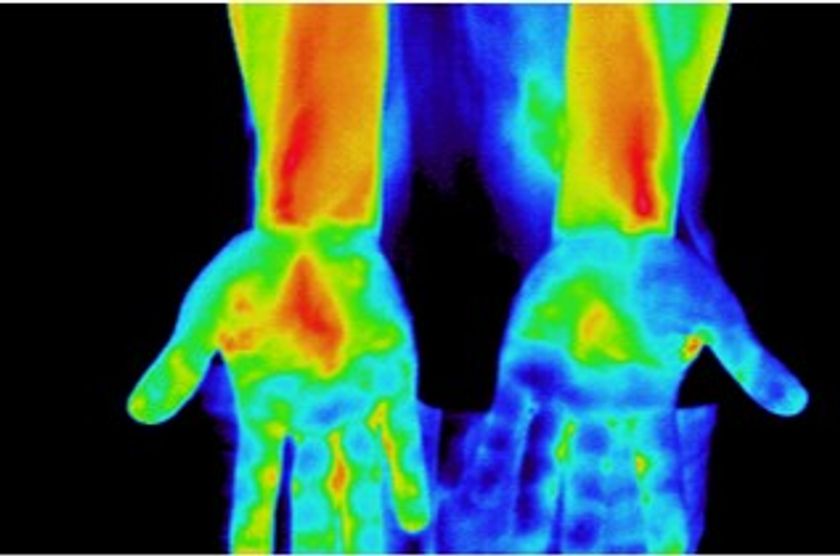

1 血流促進効果

シリカ含有率の高いオーガニック炭がもたらす輻射熱とラジウムなどの温泉鉱石により、広範囲の血流を促進します。(主要血管部を含む体表温度の変化により測定)

スパオール装着時の左右の手の温度分部